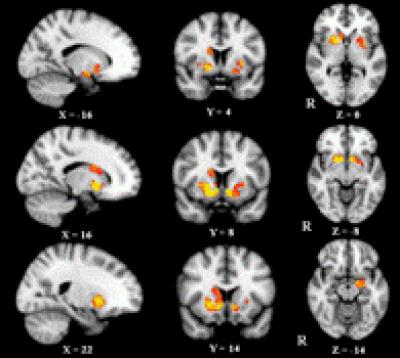

Accumulating evidence indicates that chronic pain of different etiologies is often associated with distinct gray matter volume reductions in multiple brain regions associated with acute pain processing, and gray matter atrophy critically affects the perception and modulation of chronic pain. Dr. Cuiping Mao and co-workers from Xi'an Jiaotong University in China investigated changes in gray matter volume in chronic back pain patients having different sites of pain using voxel-based morphometry. Their findings suggest that regional gray matter volume abnormalities in low back pain patients are more extensive than in upper back pain patients. Subcortical gray matter volume increases are found only in patients with low back pain. The gray matter volume increase in the basal ganglia of low back pain patients might be a reflection of the adaptation of neurons. The relevant article was published in the Neural Regeneration Research (Vol. 8, No. 32, 2013).

Article: " Differences in brain structure in patients with distinct sites of chronic pain: a voxel-based morphometric analysis," by Cuiping Mao1, Longxiao Wei1, Qiuli Zhang1, Xia Liao2, Xiaoli Yang2, Ming Zhang1 (1 Department of Radiology, the First Affiliated Hospital, School of Medicine, Xi'an Jiaotong University, Xi'an 710061, Shaanxi Province, China; 2 Department of Pain, the First Affiliated Hospital, School of Medicine, Xi'an Jiaotong University, Xi'an 710061, Shaanxi Province, China)